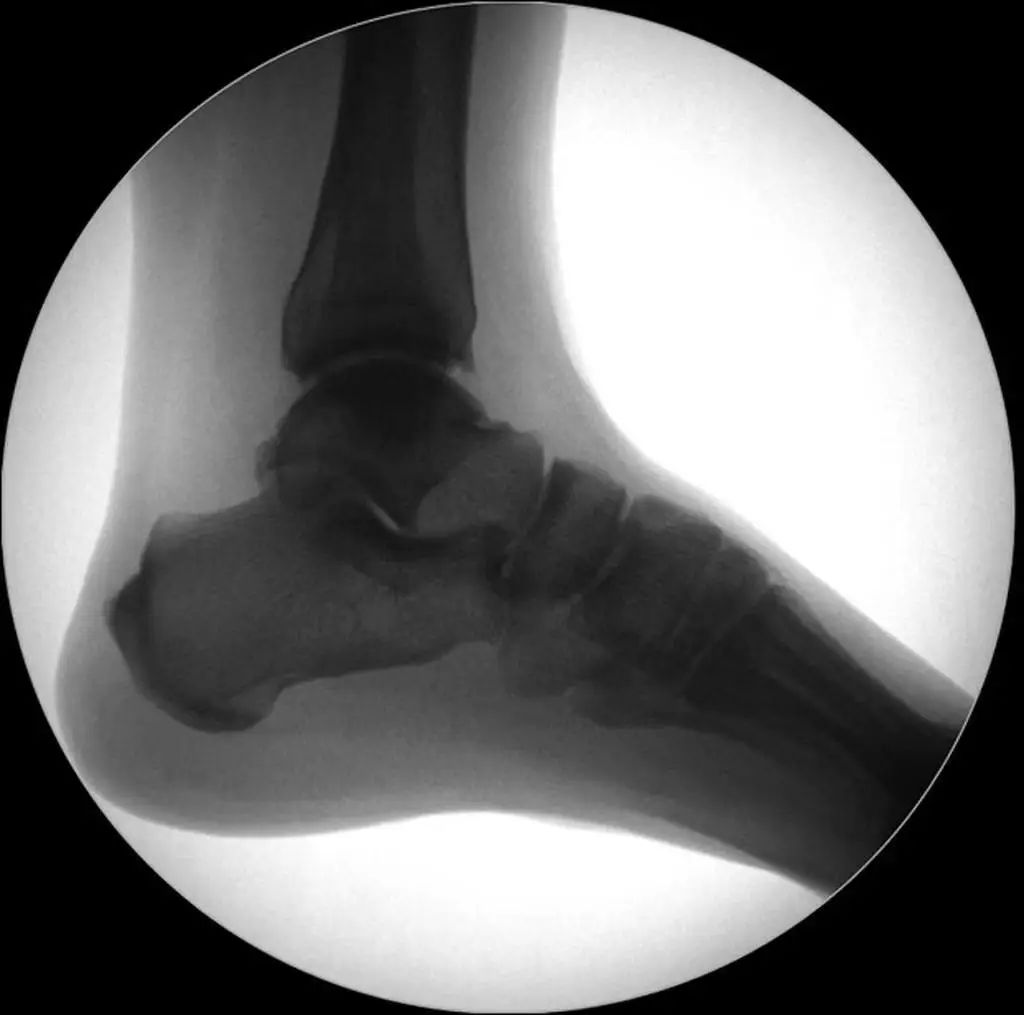

Рентгенодиагностика. Стандартная визуализирующая оценка голеностопного сустава должна включать 3 фазы: переднезаднюю (рис. 8), точку голеностопного сустава (внутренняя ротация 15°) (рис. 9) и боковую (рис. 10).

Рисунок 8 Переднее и заднее положение

Рисунок 9. Точки голеностопного сустава (15° внутренней ротации)

Рисунок 10 Боковое положение